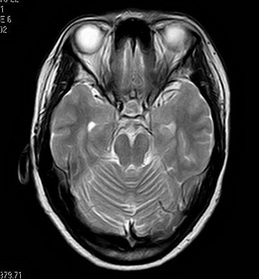

住院期间视频脑电图显示:重度异常脑电图;间期癫痫样发电,左侧颞区;先兆-肌张力障碍(右侧上肢)。头部MR提示:1.左侧海马萎缩、硬化;2.小脑轻度萎缩;3.右侧上颌窦粘膜下小囊肿。

术前MR